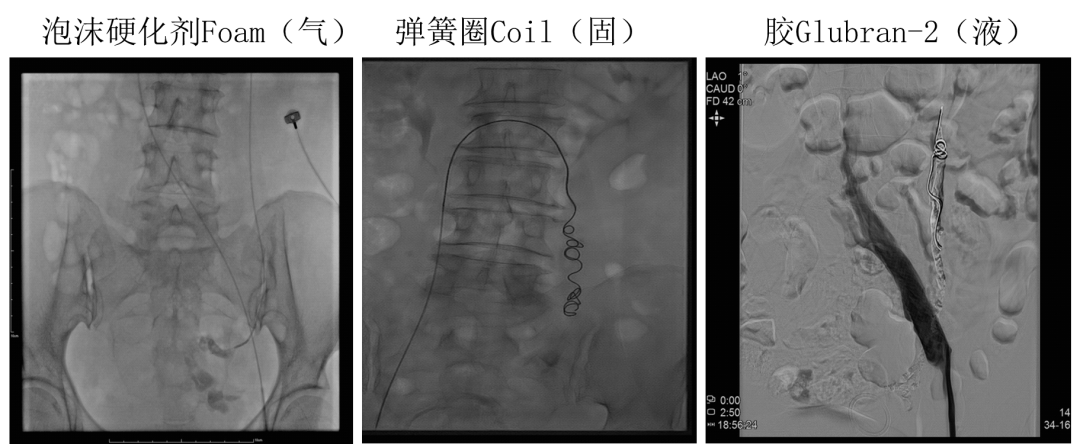

传统三明治技术(sandwich)

弹簧圈+泡沫硬化剂

Sandwich技术优化-节约版

GLUBRAN替代Onxy;

双股静脉入路:可调弯鞘解决反流支;

减少可控圈以及微导管使用;

减少费用;

减少照射;

减少移位;

减少复发;

需解决技术问题:液体栓塞材料溢流。

瘤巢优先,反流兼顾;

固液结合,密实栓塞。